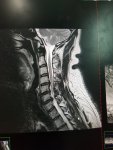

Damn brother. Based on that MRI pic, bet you have been feelin crappy for a good bit.

Grab a drink and a snack, this is a little lengthy. This all started in May of '19. Went to Thunder Valley with some friends. Layed my rifle on the ground, got down and raised my head to settle in. It was like I got electrocuted. Tingling and sensitivity from the neck down. Went away after a couple hours. Doc said that C4-C5 was likely bulging and I moved too fast. Squished the disk and it essentially punched my spinal cord. I tried going to the chiropractor and it helped for a while. I've known that I need surgery since last November. BUT while I was gearing up to handle this, my wife got diagnosed with endometrial cancer. After her hysterectomy on 12/26 the oncologist said no radiation or chemo was necessary. We took a while to recover from that ordeal and my mother-in-law died of a massive heart attack on 3-17... the day after my father-in-law's birthday. I got caught up helping deal with the aftermath of that (tons of shit to get rid of and being there emotionally for everyone) when her dad breaks his fucking foot in late May and winds up with pneumonia from sitting around. We move in with him and start to get things squared away when... cancer diagnosis number 2 happens on 9-1. Oh, I forgot to mention, Fucking Covid! Anyway. She's done with her radiation and now it's my turn. Finally. They say hindsight is 2020. Bullshit! I never want to look back on 2020.

As far as the 2 level replacements vs 3 level fusion, we discussed my options. I work in EMS and drive a ton. Running lights and siren increases the risk of an accident significantly. Replacements allow more range of motion. I will also be back to work much sooner. He agrees that a 3 level fusion puts me at higher risk of deterioration of the adjacent levels. So he will have to go back in later no matter what. With the 2 level replacements, I mostly have to worry about C5-C6. He can do a fusion of that area later. Since I'll already have the replacements in both adjacent levels, I'm less likely to have complications with them. I trust my doc. He was recommended by one of the physicians that started the pediatric ortho dept at Dayton Children's. The same doc that put rods and screws in my son. Pics included.

As far as the 2 level replacements vs 3 level fusion, we discussed my options. I work in EMS and drive a ton. Running lights and siren increases the risk of an accident significantly. Replacements allow more range of motion. I will also be back to work much sooner. He agrees that a 3 level fusion puts me at higher risk of deterioration of the adjacent levels. So he will have to go back in later no matter what. With the 2 level replacements, I mostly have to worry about C5-C6. He can do a fusion of that area later. Since I'll already have the replacements in both adjacent levels, I'm less likely to have complications with them. I trust my doc. He was recommended by one of the physicians that started the pediatric ortho dept at Dayton Children's. The same doc that put rods and screws in my son. Pics included.

Based on your MRI, your herniated discs are squeezing your spinal cord.

You should be very happy with the results. Most notice improvement right away.

The disc replacementents are becoming more and more common. They may help to preserve your neck motion as well as avoid over stressing the other nearby discs...